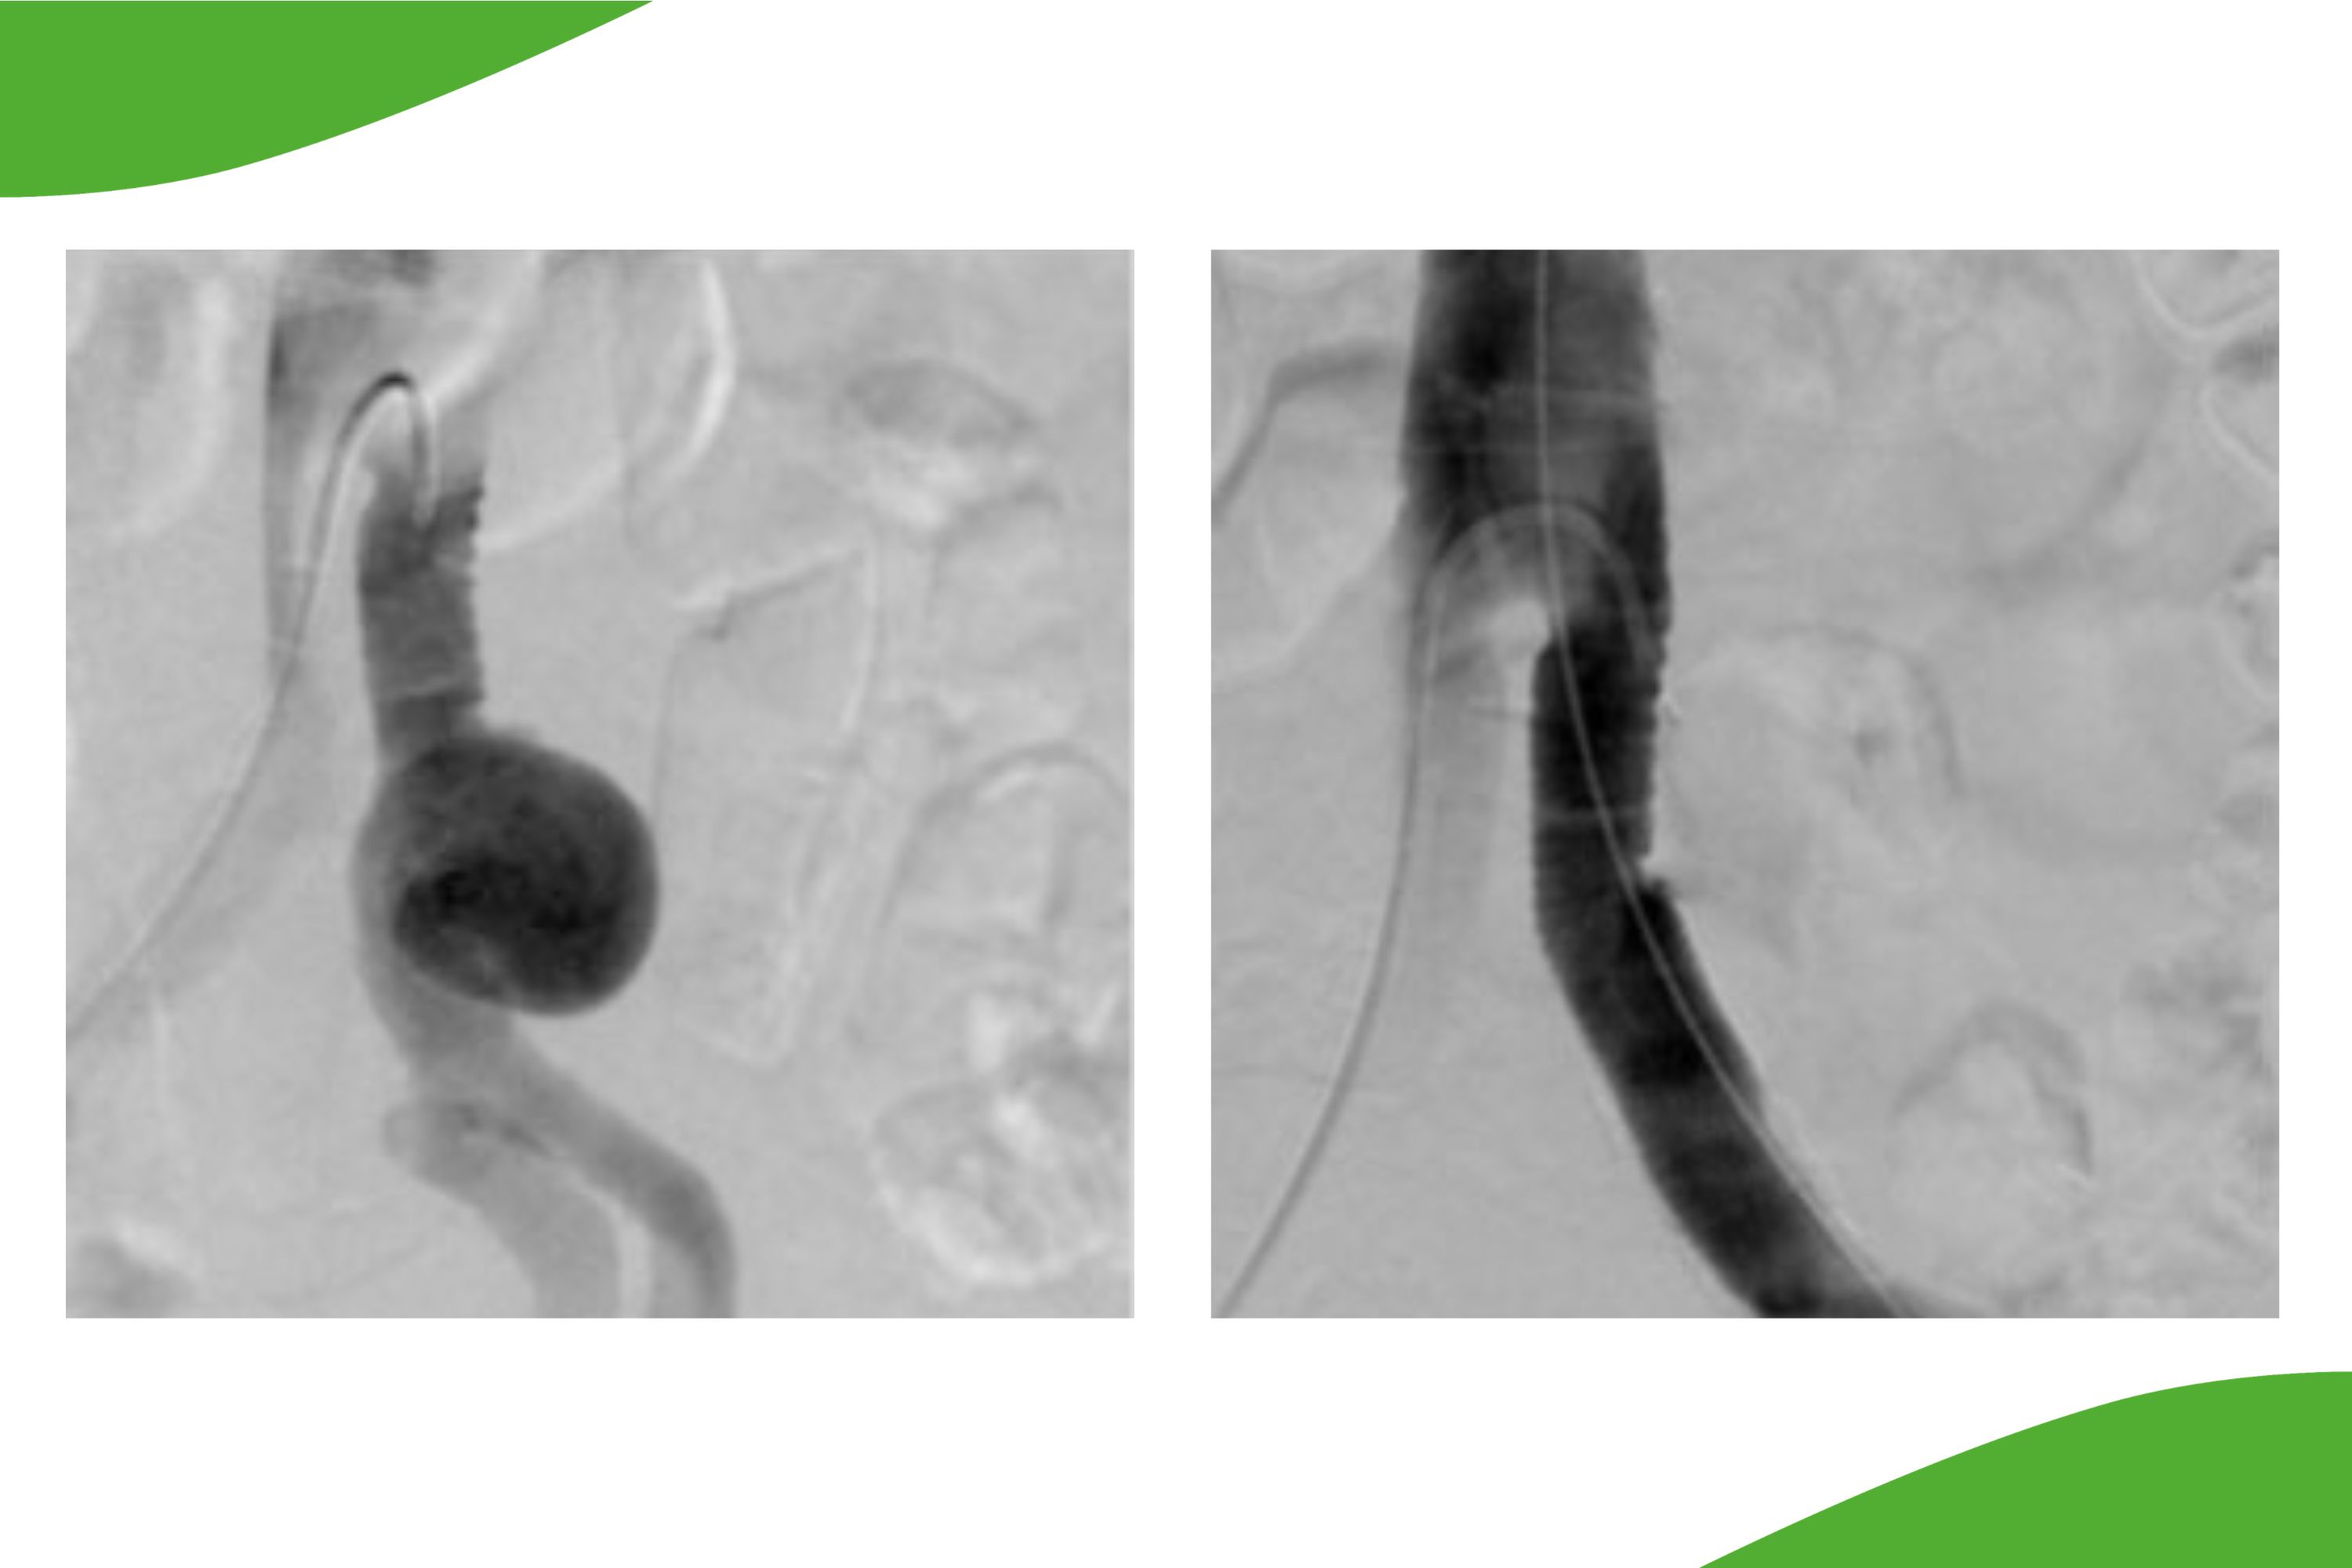

Für bestimmte Indikationen wie z.B. das Ausschalten von Aneurysmen in der Becken-Beinstrombahn oder von Gefäßverletzungen kann auch ein ummantelter Stent zum Einsatz kommen. Solche sog. Stentgrafts sind mit einer zusätzlichen Kunststoffhülle umgeben und decken damit das Aneurysma ab bzw. mit diesen Stents kann das Gefäßlumen rekonstruiert werden (Abbildung).

Links ein Anschlussaneurysma nach Y-Prothese, rechts die Ausschaltung durch Stentgraft.